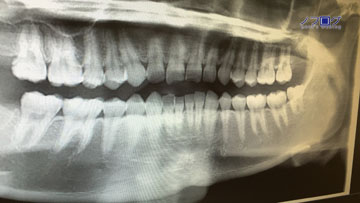

(以下、私の歯の全体のレントゲンが掲載されております。

抵抗のある方は、閲覧することを控えてください)

レントゲンも360°全部撮られた。

そこで、改めて、抜歯方法についての説明を受ける。

今回は難易度が高い。

そのため、万が一のリスクもありうるという。

歯の根っこが曲がっているため、一発で抜くことは無理。

そこで、歯を半分に割り、抜いていった。

現在、歯は28本。